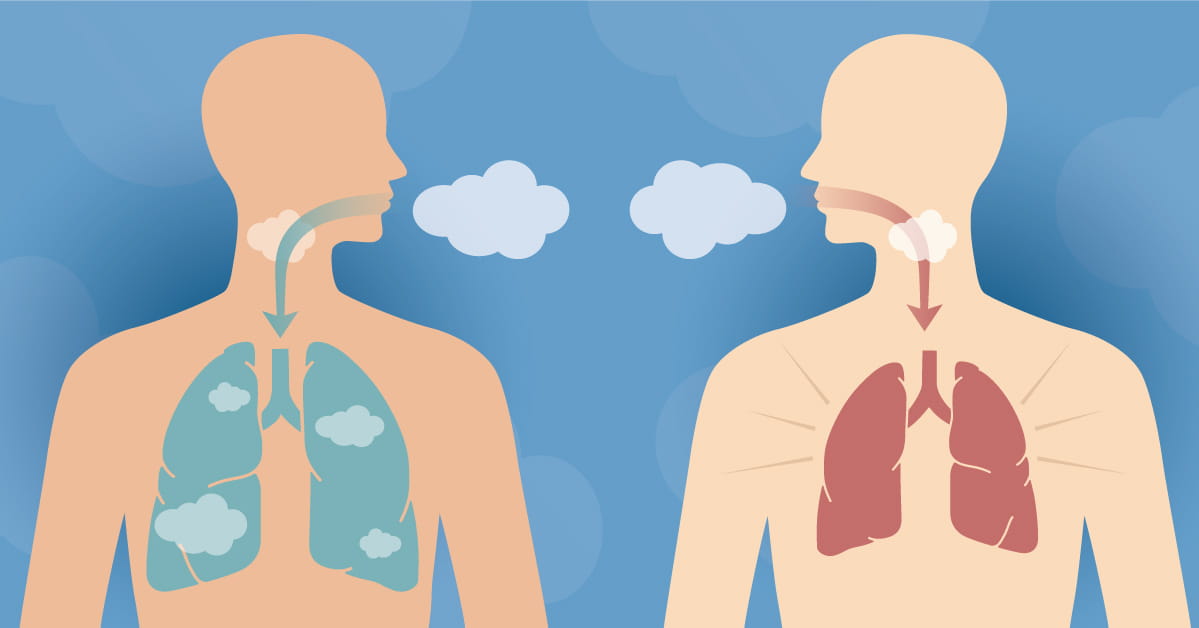

What Causes Shortness Of Breath And What Does It Feel Like